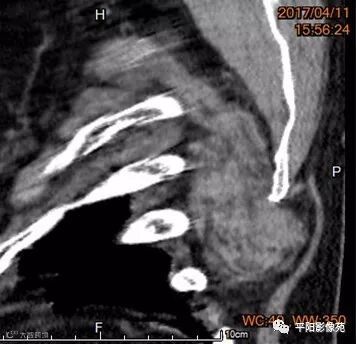

现病史: 患者3年前无意见发现左背部肿物,约鸡蛋大小,无发热、恶心、呕吐、肩背部疼痛,近3年来肿物逐渐增大,约6cm*5cm大小,未经任何治疗。

影像表现

两例患者均为左侧肩胛下实性软组织肿块,边缘模糊,质软,内为肌肉样密度及脂肪密度,以肌肉样密度为主。

CT:边界模糊,与肌肉相似的密度,病变内部可见点状、条状脂肪密度,增强扫描轻度强化或无强化。